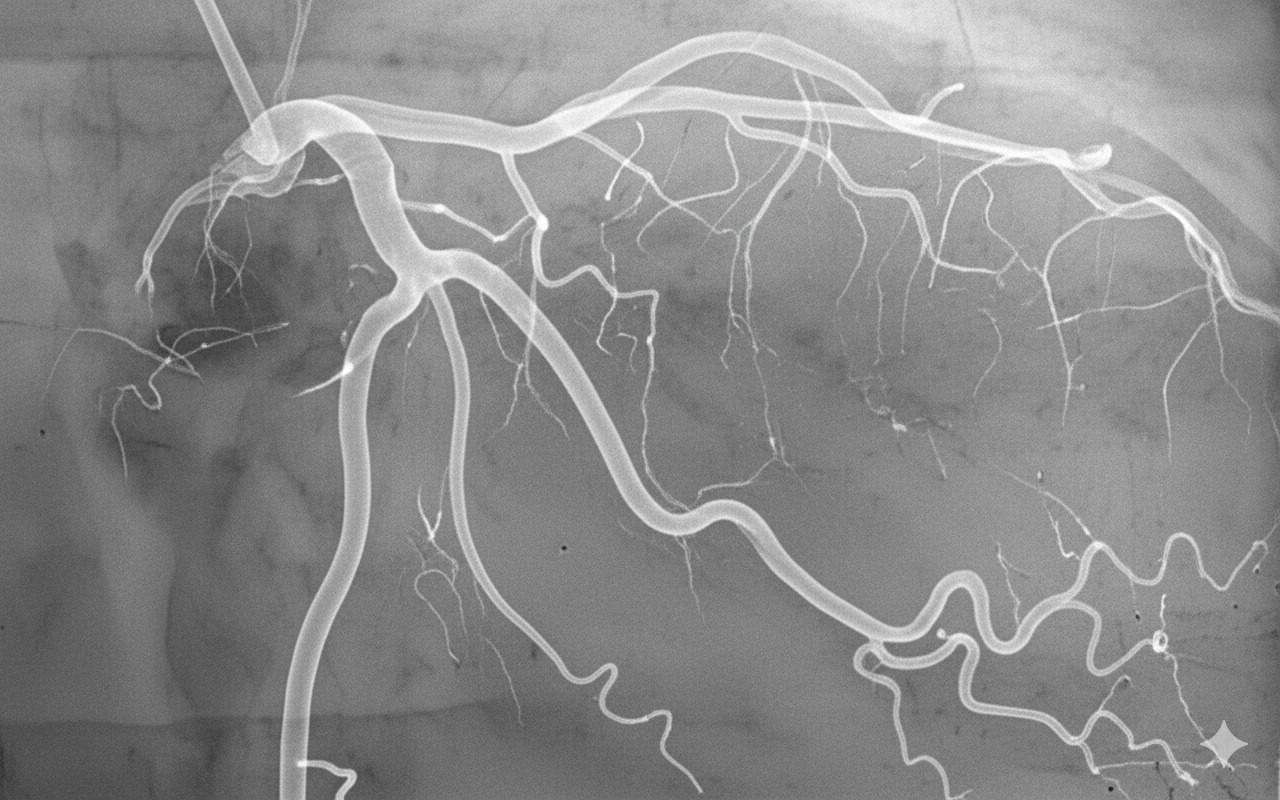

Anjiyografi

Koroner Anjiyografi ve Stent

Kalp damarlarındaki tıkanıklıkları yüksek çözünürlüklü görüntüleme ile tespit ediyor, gerekli durumlarda ilaç salınımlı stentler ile damar açıklığını sağlıyoruz.

• Bilekten (Radial) Anjiyo imkanı

• Kompleks damar tıkanıklığı tedavisi

• IVUS / FFR ile hassas ölçüm